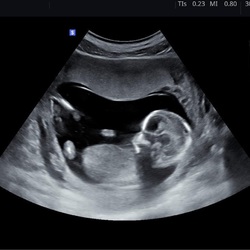

Gister bij de verloskundige de eerste echo gehad. Hartje klopte maar vruchtje was te klein voor aantal weken. Over 2 weken terug spannende tijd dus. Ik duim dat ik korter zwanger ben en de grootte van het vruchtje dan wel klopt...